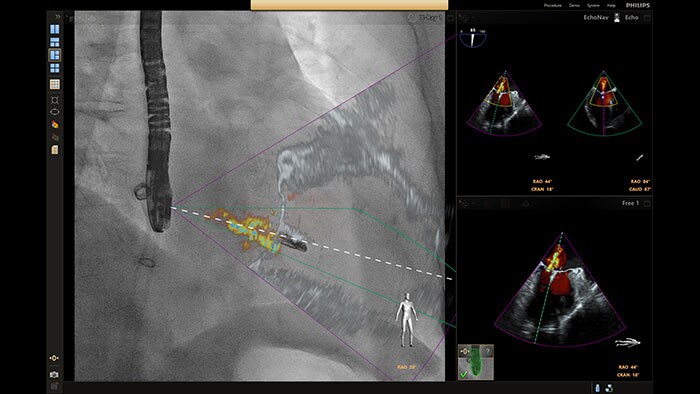

Live image guidance and fusion — EchoNavigator

Automatically fuses live 3D TEE and live X-ray in real time, allowing you to intuitively guide your device in the 3D space more quickly and efficiently when every move counts.